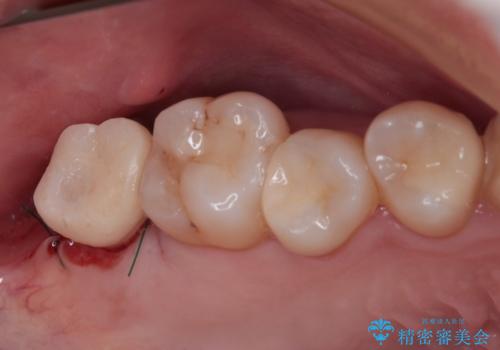

放置したむし歯 抜歯後にインプラントで補綴治療

- 長年放置しているむし歯を気にして来院された患者様です。

外側を向いている上顎の奥歯は歯ブラシが十分に届かないため、むし歯となるケースが多いのですが、今回むし歯となってしまった歯がそれで、ボロボロになって根だけが残っている状態でした。

患者様と相談し、抜歯をした上でインプラントによる補綴治療を行うこととしました。

抜歯後に不快感は消失したのですが、手前の歯にあるむし歯が痛み出してきたため、セラミックインレーにて修復治療を並行して行いました。